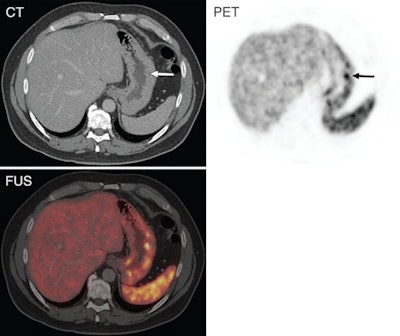

Neuroendocrine tumors recurred in 29 (46%) of the 63 patients, according to the reference standard. The median time between curative surgery and recurrence was 41 months, ranging from three to 348 months.

PET/CT with Ga-68 DOTATATE correctly identified 26 of the 29 patients with recurrent NET, and it ruled out NET recurrence in 28 of 34 patients. This translated to a sensitivity of 90% and specificity of 82%, the authors wrote.

Six patients had false-positive results and three had false-negative findings, resulting in a positive predictive value (PPV) of 81% (26 of 32), negative predictive value (NPV) of 90% (28 of 31), and accuracy of 86% (54 of 63) for Ga-68 DOTATATE PET/CT.

Some subgroups were evaluated in the study: One group underwent regular follow-up despite no indication of increased levels of tumor markers or clinical suspicion of NET recurrence. Among these individuals, Ga-68 DOTATATE PET/CT helped identify seven of eight patients with recurrent NET and helped exclude recurrence in 21 of 22 patients. Ga-68 DOTATATE PET/CT also led to false-positive and false-negative results in one patient each, indicating PPV of 87%, NPV of 95%, and accuracy of 93%.

Among a subgroup of 45 patients with gastroenteropancreatic NET, Ga-68 DOTATATE PET/CT results were comparable to findings for the entire study cohort. Sensitivity was 94%, specificity was 89%, PPV was 85%, NPV was 96%, and accuracy was 91%.

"Overall, these findings indicate a substantial value of Ga-68 DOTATATE PET/CT in the follow-up of NET patients," Haug and colleagues wrote. "However, positive findings on the PET/CT scan have to be considered with caution, as rare instances of false-positive results may occur, for instance due to inflammatory changes."